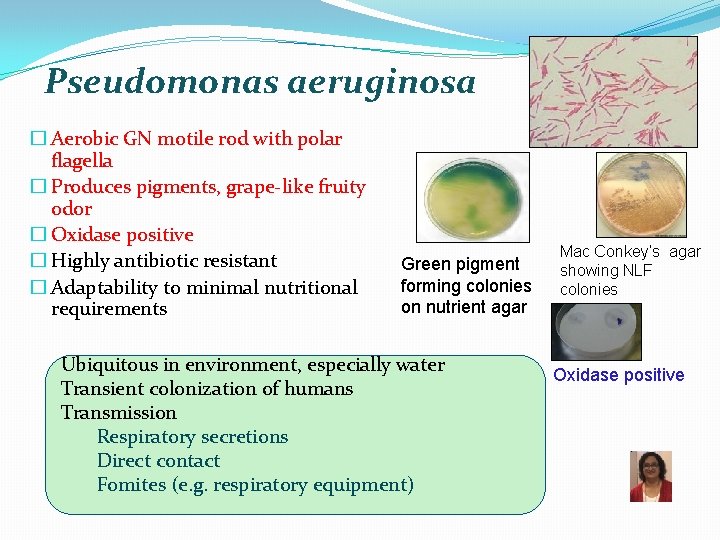

Pseudomonas aeruginosa � Aerobic GN motile rod with polar flagella � Produces pigments, grape-like fruity odor � Oxidase positive � Highly antibiotic resistant � Adaptability to minimal nutritional requirements Green pigment forming colonies on nutrient agar Ubiquitous in environment, especially water Transient colonization of humans Transmission Respiratory secretions Direct contact Fomites (e. g. respiratory equipment) Mac Conkey’s agar showing NLF colonies Oxidase positive